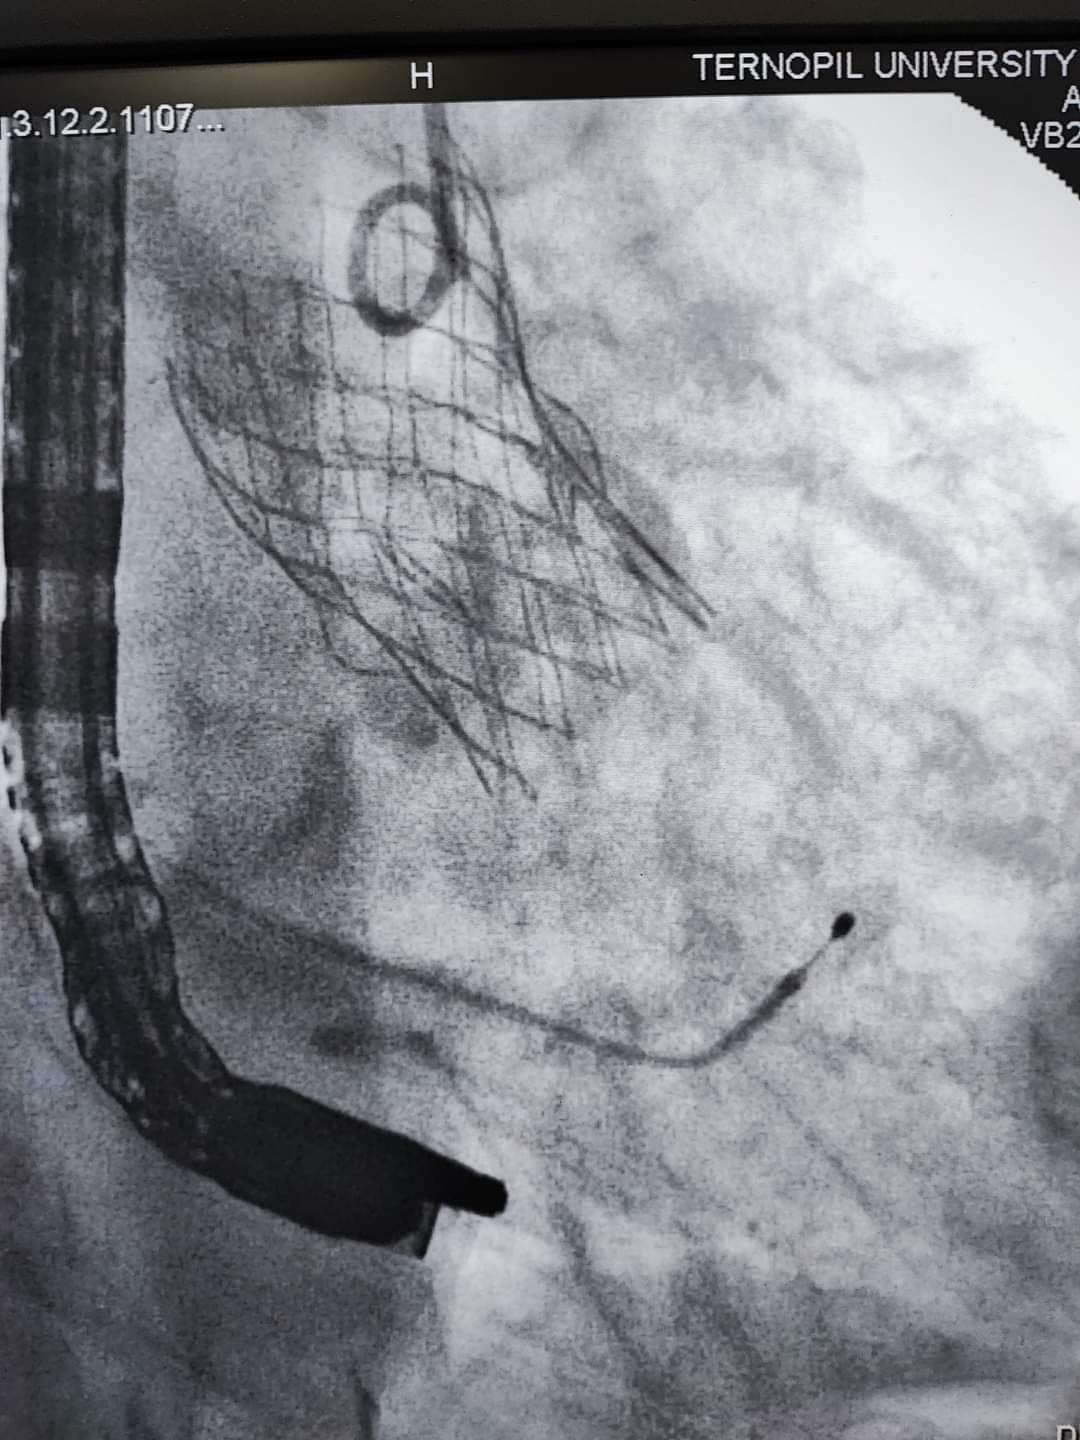

«Одна з них має важке викривлення хребта, внаслідок якого анатомічно складне положення серця, аорти та інших внутрішніх органів. Це практично унеможливлювало виконання заміни клапана іншим доступом окрім трансапікального, що, власне, було й проведено. Суть операції полягає в тому, що на працюючому серці виконується невеликий отвір, на якому через трубку-катетер по провіднику вводиться згорнутий клапан. Позиціонування контролюється як рентгенівським зображенням, так і черезстравохідним ультразвуковим датчиком. Після імплантації хірург затягує вузол навколо отвору і вшиває рану. Крововтрата є мінімальною», – наголосив Богдан Маслій.